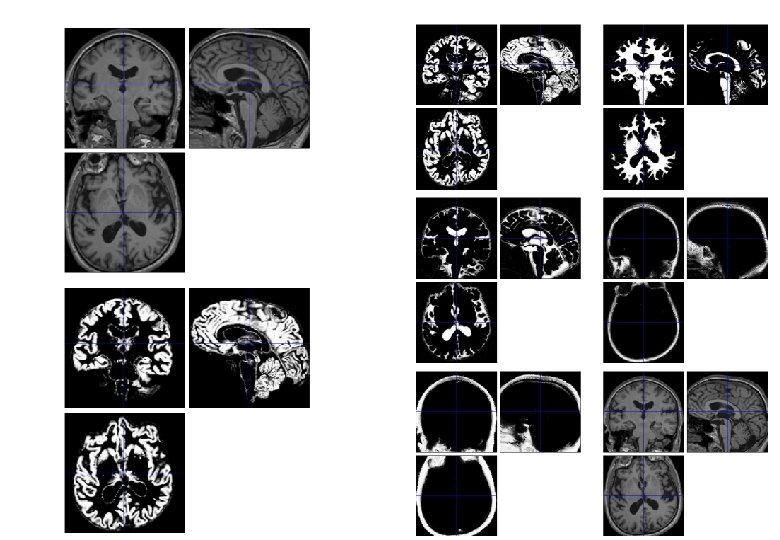

Simultaneous registration of GM to GM and WM to WM Subject 1 Grey matter White matter Subject 2 Template Grey matter White matter Subject 4 Subject 3

Template Initial Average Iteratively generated from 471 subjects Began with rigidly aligned tissue probability maps After a few iterations Final template